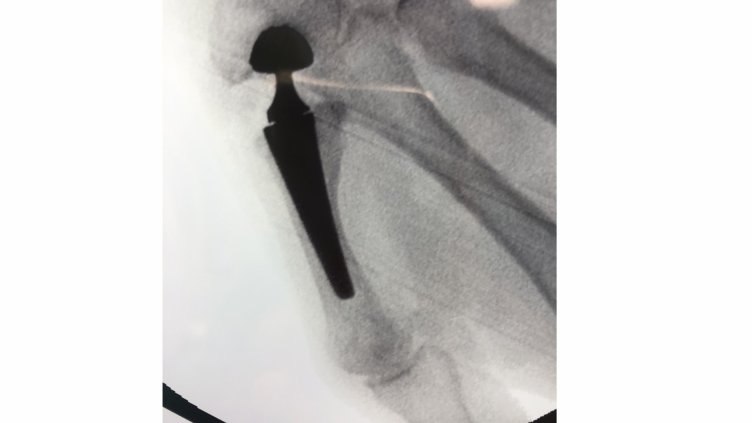

Така изглежда супермодерната двойно подвижна става, умален вариант на иновативната тазобедрена изкуствена става, която е съвсем отскоро на световния пазар.

Ставата е от тип „ dual mobility” – двойно подвижна и може да се счита за умален вариант на иновативната тазобедрена изкуствена става, която е съвсем отскоро на световния пазар.